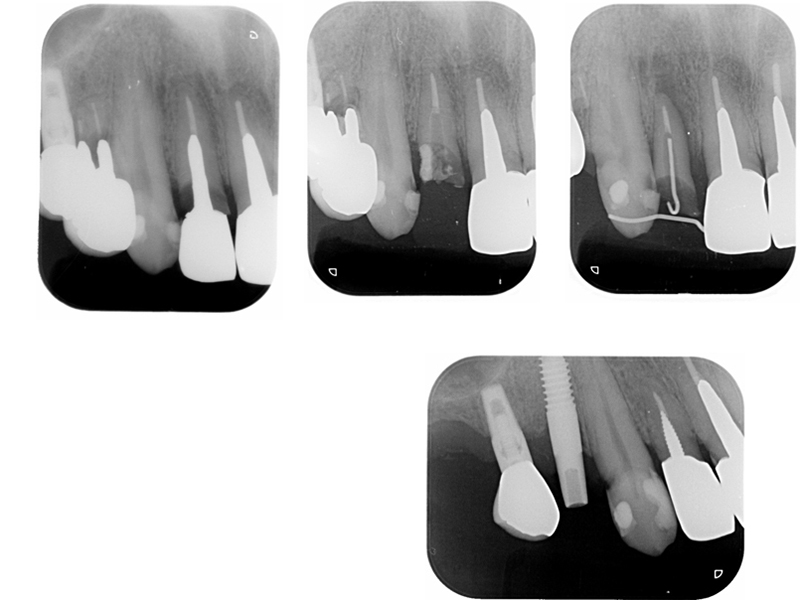

▼ ケース4.Upright症例

初診

治療中

before

after